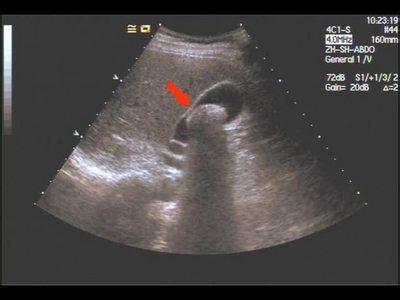

胆结石图片